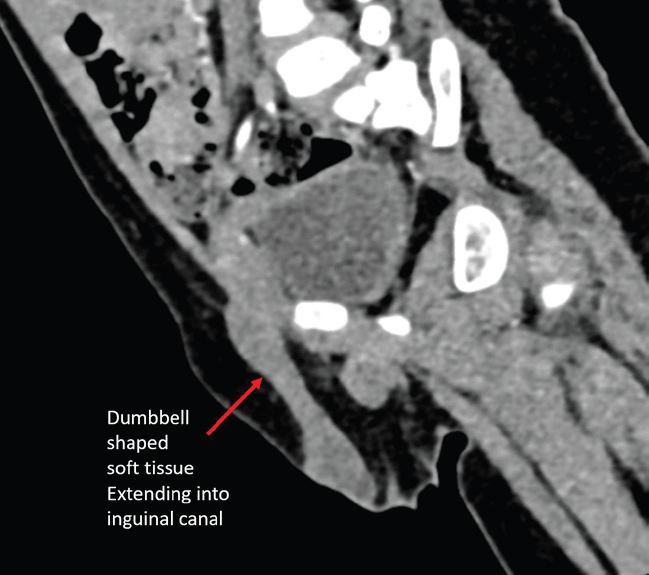

failed to identify the left testis. Contrast-enhanced CT (CECT) pelvis

revealed a dumbbell-shaped enhancing soft tissue density extending

from the right inguinal canal into the scrotum [Figure 1,2,3].

Figure 2: Oblique sagittal reconstruction of CECT pelvis demonstrating

dumbbell-shaped soft tissue density in the inguinal ring tracking into the right

scrotum.